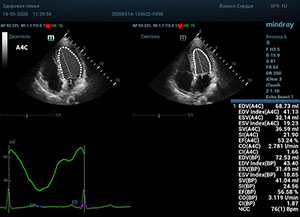

Что могут предложить современные приборы? Приборы нашего времени являются мощными вычислительными машинами, способными обрабатывать полученную информацию даже без помощи человека. Система автоматического вычисления фракции выброса – AUTO EF на приборах серии Resona компании Mindray сделает все за вас. За пару секунд прибор сам отыщет нужную фазу сердечного цикла и произведёт измерение и расчеты, а также покажет график изменения объема в сердечном цикле. От Вас требуется только получить качественное 4С и 2С сечение. Впрочем, прибор всегда оставляет возможность коррекции, если доктор имеет свое мнение на расположение точек планиметрии или момента измерения по ЭКГ каналу.

С появлением В режима реализовалась возможность визуализации всех сегментов миокарда из парастернальных и апикальных сечений. Метод Teicholtz в широкой практике сменился методом дисков. Метод дисков, или метод Simpson, позволяет разбить левый желудочек на 20 дисков, с расчетом объема каждого из них. Используя 2 перпендикулярных сечения, апикальные двух и четырех камерное, мы приближаемся к значению реального объема левого желудочка. Исследователь обводит интерфейс эндокард – кровь в фазу диастолы и фазу систолы. Линия простирается от кольца митрального клапана и до кольца митрального клапана, четко разграничивая объем желудочка от предсердия. Для достоверного изменения необходимо использовать ЭКГ канал.